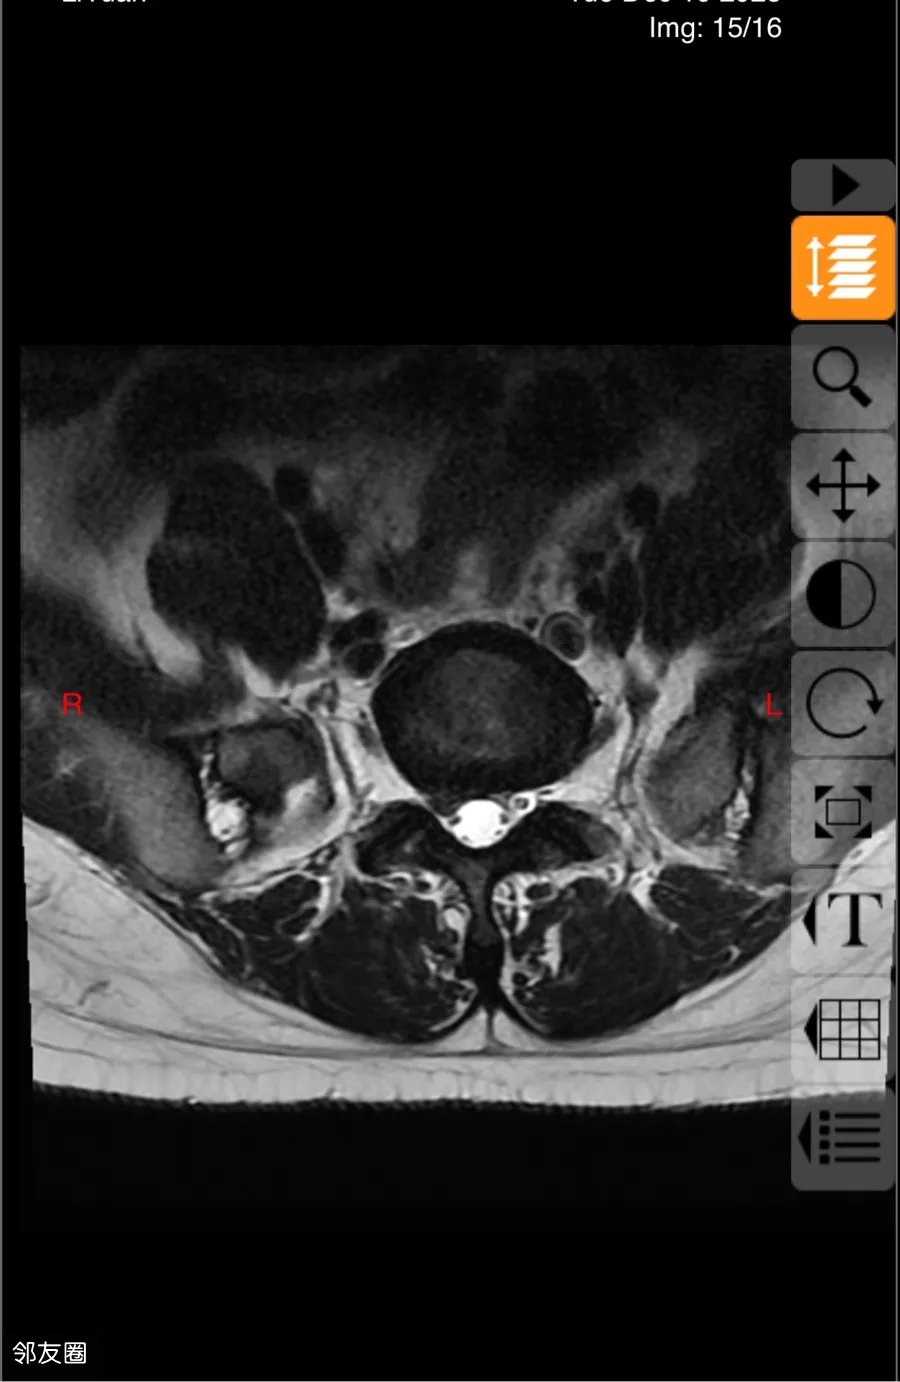

腰间盘突出!压迫神经!求救

最近一直再被腰突困扰!去了朝阳,北医三院,医生都是建议手术。各位大神们,有没有推荐的神医,最好离东坝不远的地方,出去一趟快要了小命儿了,拜托各位了

#腰椎间盘突出